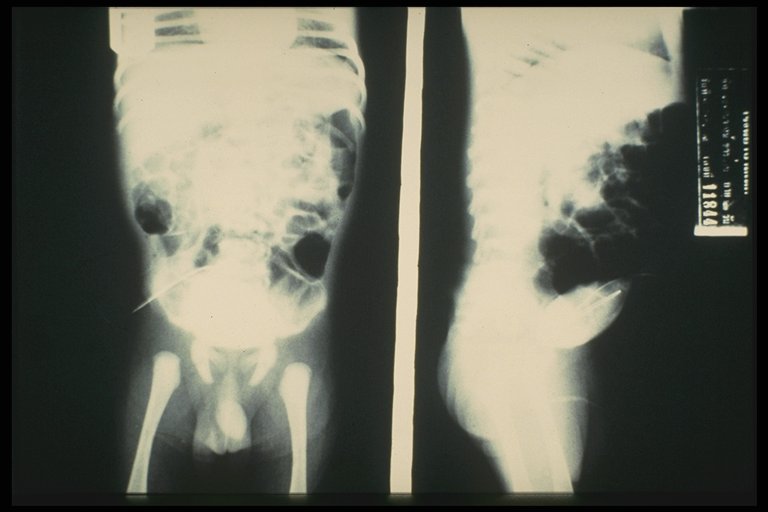

Fistulogram in a child with umbilical hernia and fistula demonstrates the connection to the intestine

Fistulogram demonstrated the tract connected between the umbilicus and the intestine